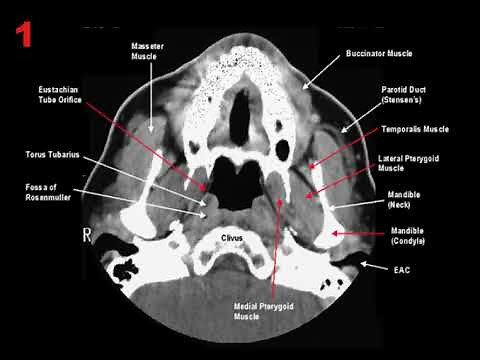

CT Neck - Neck

Scan of Pharynx Larynx - CTA Head and Neck Anatomy

- How to Read a Head and

Neck CT Course - Trachea Esophagus On

CT Scan Neck - Axial CTA